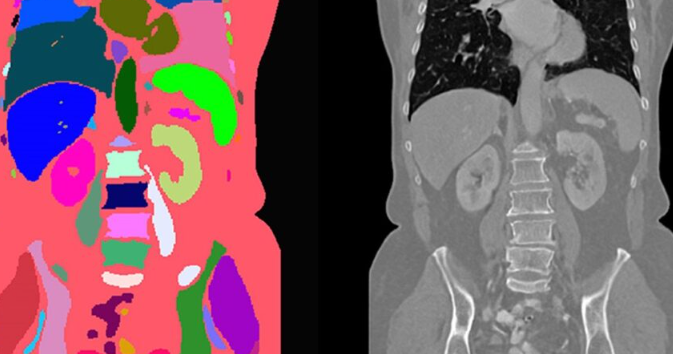

在医疗行业的深度变革中,3D扫描技术作为数字化的起点,为后续的增材制造奠定了精准的基石。不同于传统的石膏取模或手动测量,杰呈工厂采用工业级高精度3D扫描设备,能够捕捉亚微米级的解剖结构细节,为生产符合ISO 10993与USP VI级标准的生物相容性组件提供了原始依据。

杰呈工厂在实战中积累了丰富的行业案例,将3D扫描获取的云点数据转化为高性能的医疗终端产品。在手术导板领域,我们配合外科医生通过扫描数据预判手术路径,使复杂骨科手术的出血量平均降低约15%,手术时间缩短近20%。针对康复领域的矫形器与假肢,利用3D扫描对患者残肢进行全方位建模,制造出的轻量化接受腔比传统产品减重约30%,极大提升了患者的佩戴舒适度与活动灵巧性。